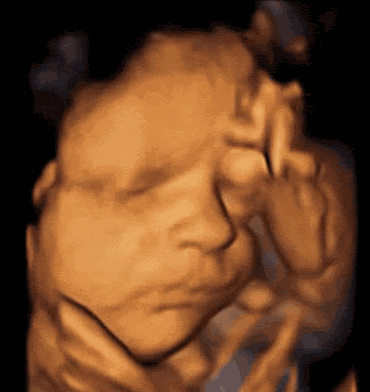

第二,四维前1、2周,多和胎宝宝沟通。

孕妈约好四维后,可以在四维前1、2周就开始和宝宝说话,请宝贝配合医生一些。

胎儿在第8周耳廓已经形成;在孕25周,胎儿的传音系统基本发育完成;孕28周时,胎儿的传音系统已经充分发育完成,并会发生听觉反应了。

因此准爸爸、准妈妈平时也可以多和胎宝宝说说话、唱唱歌、讲讲故事。